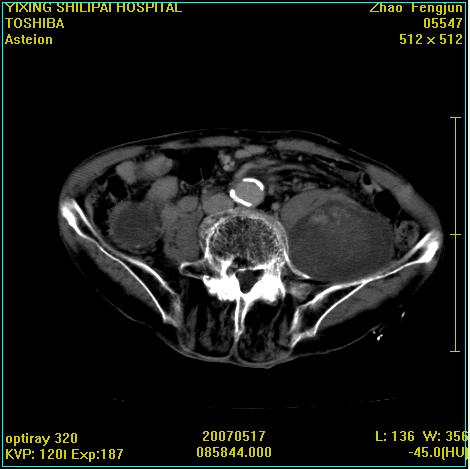

考虑:1、左侧腰大肌囊实性占位性病变(囊性神经根鞘瘤?);

2、右侧兰尾区囊性占位性病变(兰尾囊肿?囊腺癌?类癌?)

以下是引用xiaoniu在2007-5-26 10:45:00的发言:[br]腰大肌的病变应该没有问题,增强扫描还有轻度强化及细小血管影入内,应该排除脓肿,考虑占位性病变,腰大肌的占位多考虑:神经源性肿瘤。另外腹主动脉下端有真假腔的强化,考虑:主动脉夹层。[br][br][本贴已被 xiaoniu 于 2007-5-26 10:46:39 修改过]

以下是引用老爱克斯新网客在2007-5-26 18:26:00的发言:[br]1左下腹囊实性占位肿块,增强后不均匀强化,位于脊柱旁,椎体骨质无破坏软组织无肿胀,考虑神经源肿瘤神经鞘瘤可能大,2右下腹囊性占位性病变,增强后囊壁强化,考虑阑尾囊肿或囊腺瘤,